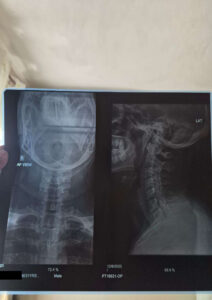

Varun, 31 ans, souffre d’une hernie discale cervicale dégénérative C4-5 avec radiculopathie. Financièrement, son traitement, son billet d’avion, son hébergement et son allocation de subsistance coûteront Rs 1,148,256 .